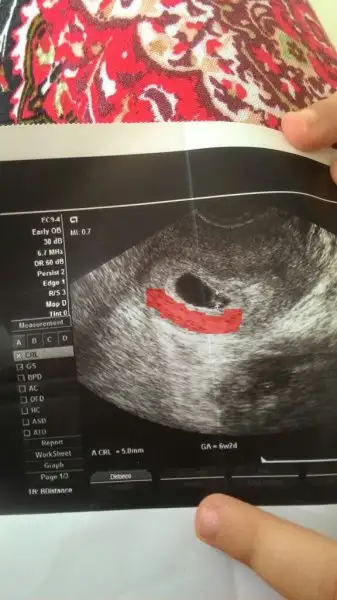

Ramzi Teorisi ve cinsiyet tahmini ( tutma olasılığı %85 miş )

Benim de solda ama bugün öğrendim ki kız bu tutmadı bende :) bir tek cin takvimi tuttu ve ben hep kız hissediyordum allah gönlüme gore verdi

Senin plasenta solda miydi cnm,foto varsa at.benimde 2.kızımda kızım kesenin sağındaydı plasenta soldaydı kızımda bende de tutmadı.bak fotosu

kızının plasentası daha belirgin. güzel çizmişsin yalnız canım plasenta biraz daha sağ yukarı doğru uzanmış. benim gözümle ramzi kızında tutmuş. karından usg diye hatırlıyorum.